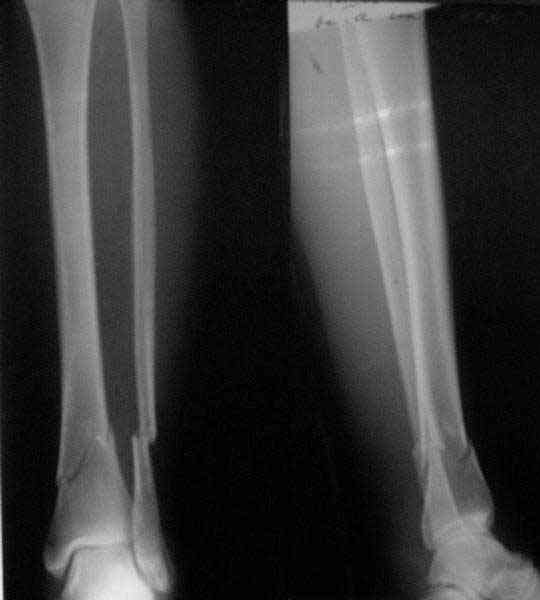

In delayed cases acute length restoration performed only in the tibia may leave the fibula shortened thus change the mortise. So it is reasonable to restore length of both bones simultaneously by distractor and fix the fibula not with open reduction and plating but just by a single perQ screw. Example attached.

[ Ответить ]